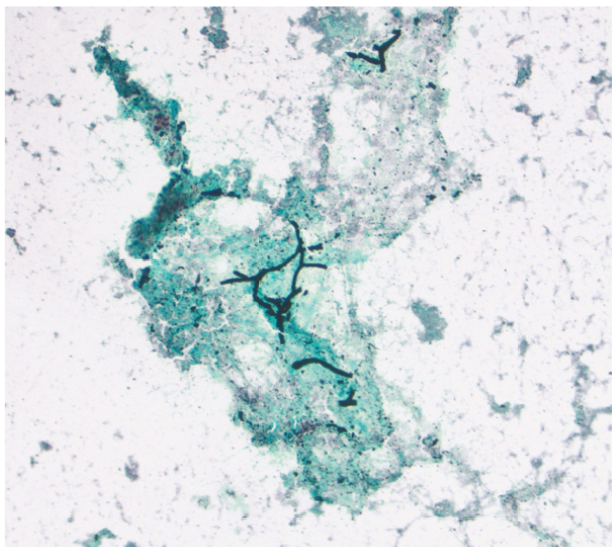

A Rare Diagnosis of Nasopharyngeal Papillary Adenocarcinoma - Thyroid Like Type

F Rhana Mousavi, Abanoub Gabra, Nick A Hirad and Alan Schiller. 6(5): 22-27.